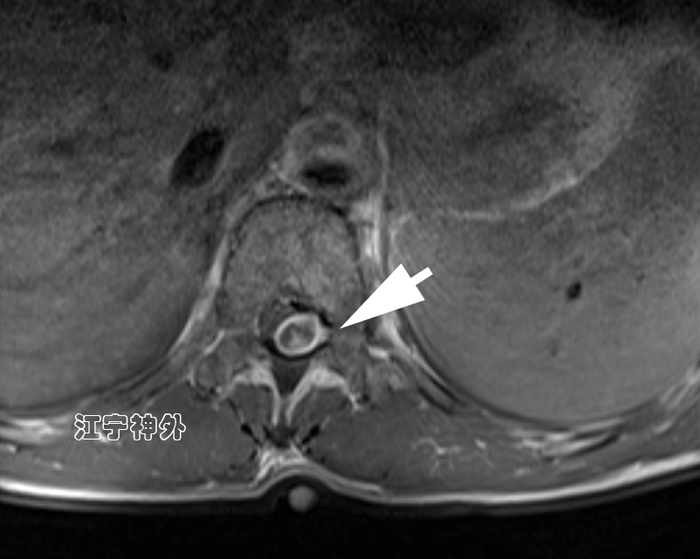

郑主任阅片发现,肿瘤位于胸10水平,属于髓外硬膜下病变,增强不均匀,边界清晰,位于脊髓的左后,脊髓被推向右前方。

经过术前准备,于2月3日在全麻下行肿瘤切除术,手术非常顺利,肿瘤完整全切,根据神经电生理监测,脊髓和神经根保护良好。

术后磁共振显示肿瘤全切,无任何残留;术后两周拆线出院,行走、大小便功能正常,无神经功能缺损。术后病理提示神经鞘瘤。